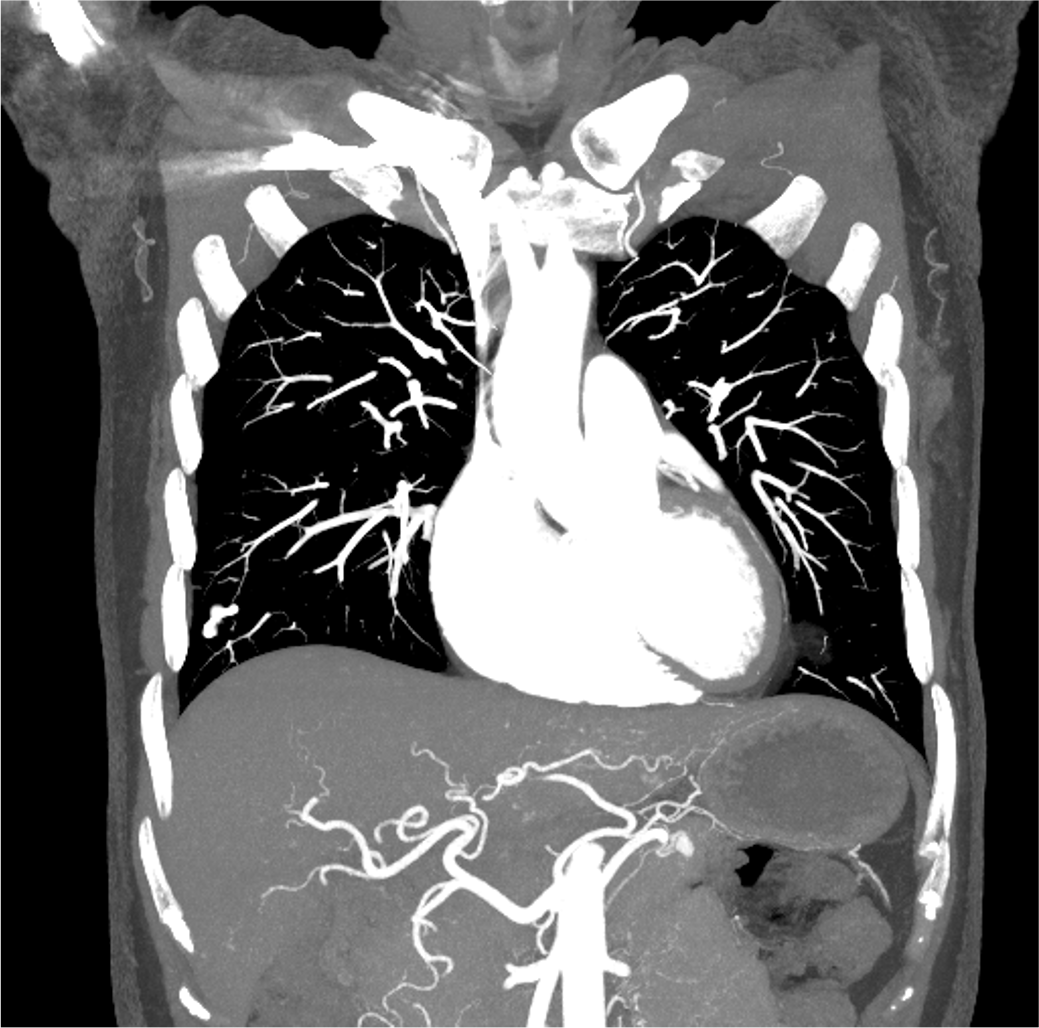

検診で指摘された肺病変のCT精査にて、肺の動静脈奇形(AVM)と診断された。精査および加療目的で当院に紹介され、術前精査のための造影CTを施行した。造影CTにて、膵尾部にAVMを認めた。その後、肺AVMに対するコイル塞栓術が施行され、その際に膵AVMも血管造影にて精査が行われた。膵AVMによる症状はなく経過観察とされ、外来にて定期的にフォローアップされている。

オスラー病(遺伝性出血性毛細血管拡張症、HHT)は、全身の血管に異常を生じる、常染色体優性遺伝の遺伝性疾患であり、特に肺・脳・肝臓・消化管などの動静脈奇形(AVM)や、鼻出血、口・指・鼻などの毛細血管拡張を生じることで知られる。膵臓にも30-60%の患者に血管病変を生じるとされ、その約2/3が毛細血管拡張、約1/3がAVMと言われている。

単純CTでは膵臓の異常血管の描出は困難であり、造影CTは診断において重要である。膵臓のAVMにおいては、(1)拡張・蛇行した供血路、排血路といった異常血管の描出や、(2)動脈相で門脈系の血管の早期造影効果が認められ、診断のポイントとなる。造影CTは血管造影と比較して侵襲性が低く、膵実質の全体の評価にも適しているため、精査のみならず、フォローアップにも用いやすい。

CT技術や撮像プロトコル設定について